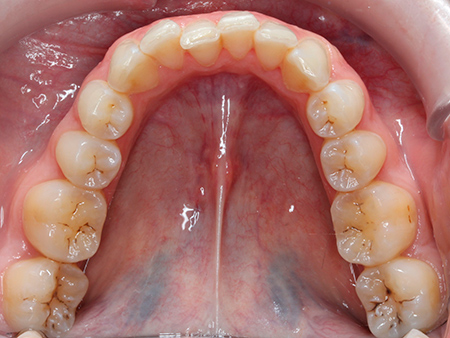

Ana vino a la clínica porque no estaba contenta con su sonrisa. Ella había llevado brackets anteriormente pero, al no haber usado la retención de manera adecuada, los dientes habían vuelto a su posición inicial.

Después de analizar su caso, nuestro equipo de ortodoncistas le aconsejó abordar un tratamiento de ortodoncia. Su objetivo era corregir el apiñamiento y la sobremordida que presentaba tanto en la arcada superior como en la inferior.

Tras un procedimiento de ortodoncia con alineadores transparentes Invisalign de 21 meses de duración, Ana ya disfruta de una sonrisa estética y funcional.